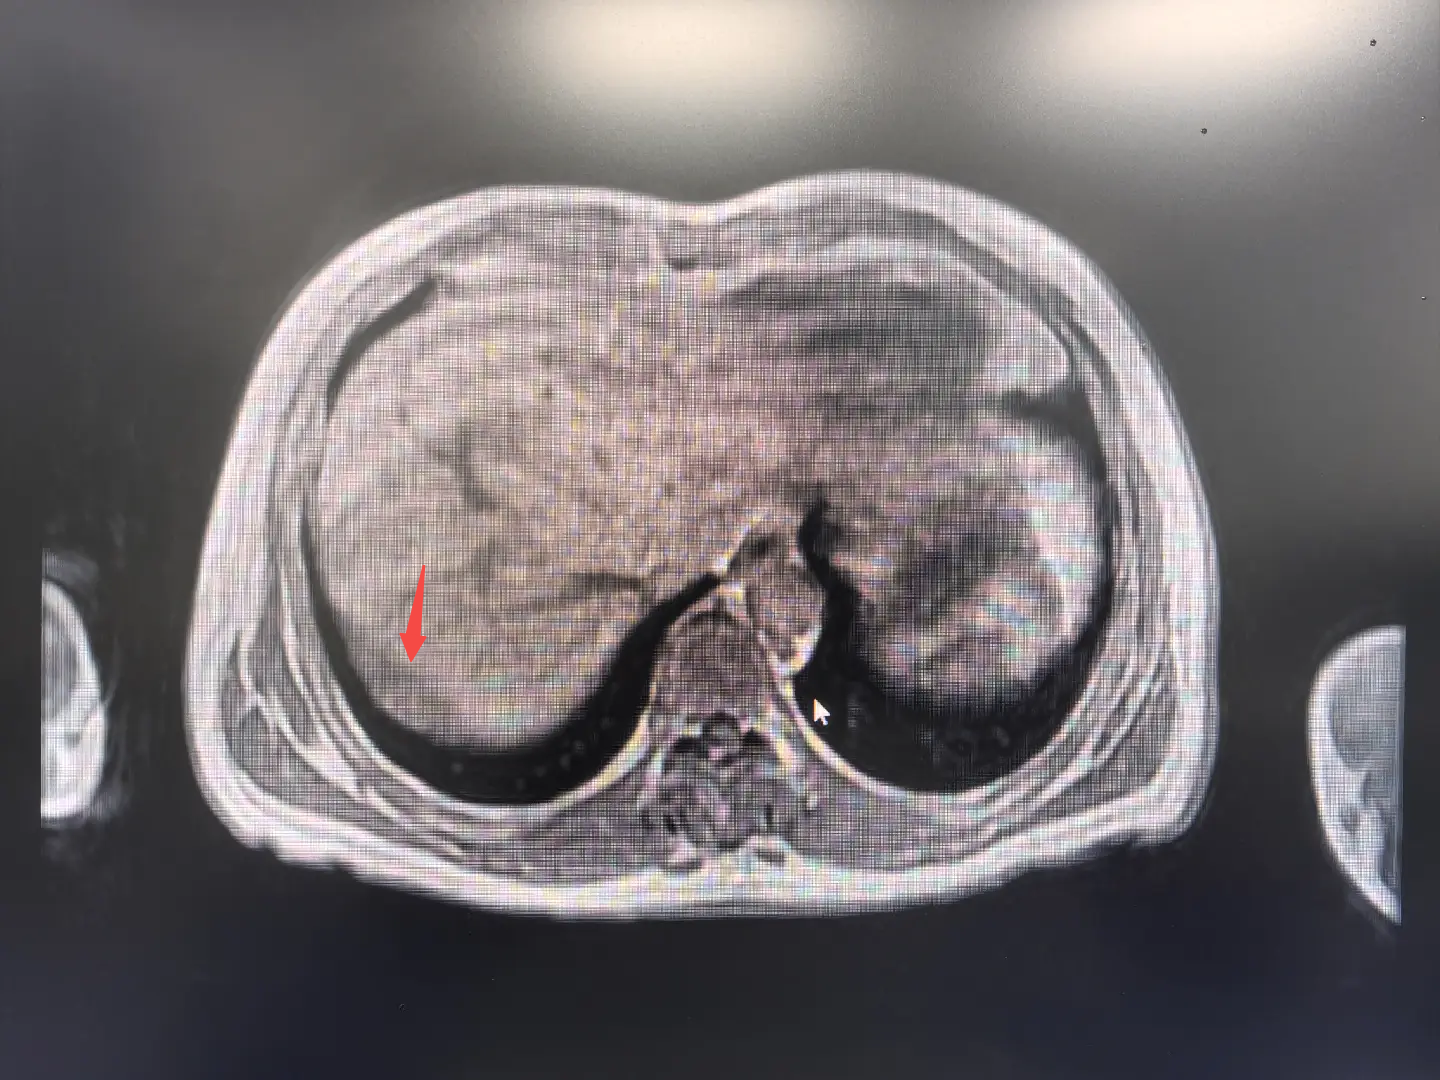

近期,李爷爷在体检中发现肿瘤标志物CEA升高,经全身PET/CT检查,发现其右膈下腹膜有一处新发病灶,糖代谢活性增高(提示肿瘤可能性大),且与肝右后叶包膜分界不清,临床考虑为腹膜转移性病变。

在游离肝周粘连后,团队不仅找到了预定的目标——那个约5cm*4cm的膈肌表面腹膜下的“炸弹”(术前发现的新病灶),还意外在肝脏上发现一个0.5cm的“小地雷”(术前没发现的微小病灶)。经现场讨论,团队决定将两个病灶一并切除。

主刀医生在距离肿物边缘1cm处用电凝勾烧灼出预切线,小心翼翼地将它从膈肌上剥离。果不其然,肿瘤和膈肌长在了一起。